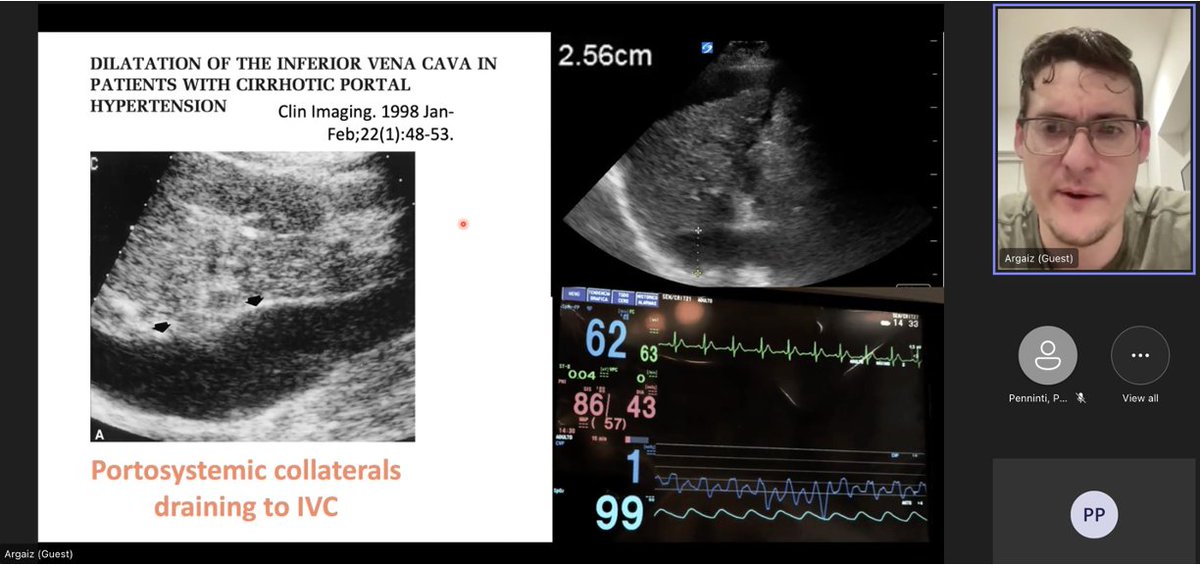

A huge thank you to @ArgaizR for joining us for our @UPMC Hepatology Conference to talk about POCUS in cirrhosis and AKI! A masterclass in physiology and a paradigm shift in how to approach an incredibly common and challenging problem for our patients. #livertwitter